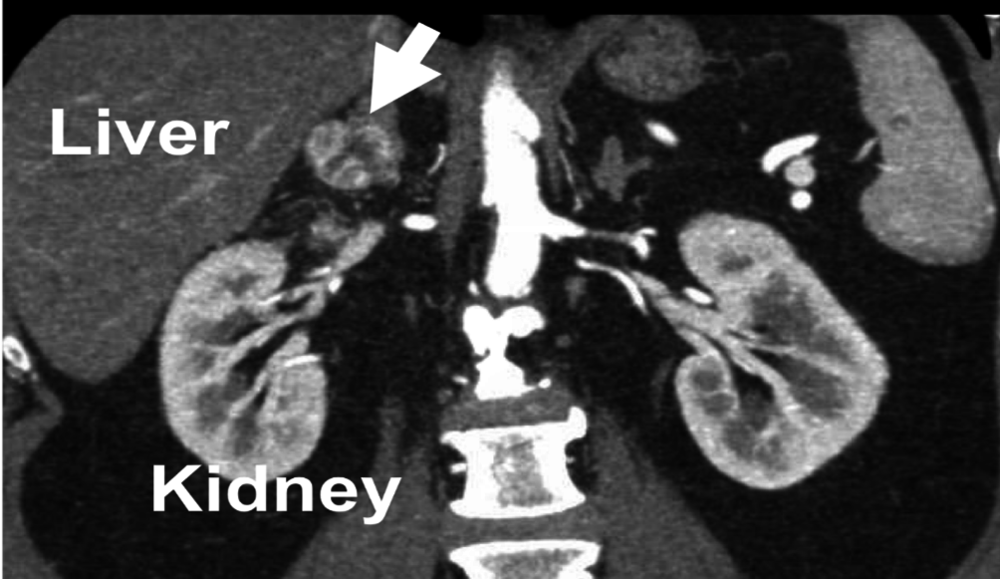

Figure 2. CT scan demonstrating an adrenal metastasis from renal cell carcinoma (RCC, kidney) to the right adrenal gland (arrow). This tumor was removed using the Mini Back Scope Adrenalectomy (MBSA), which is the best adrenal operation. An adrenal metastasis (arrow) from a lung cancer, removed by Dr. Carling